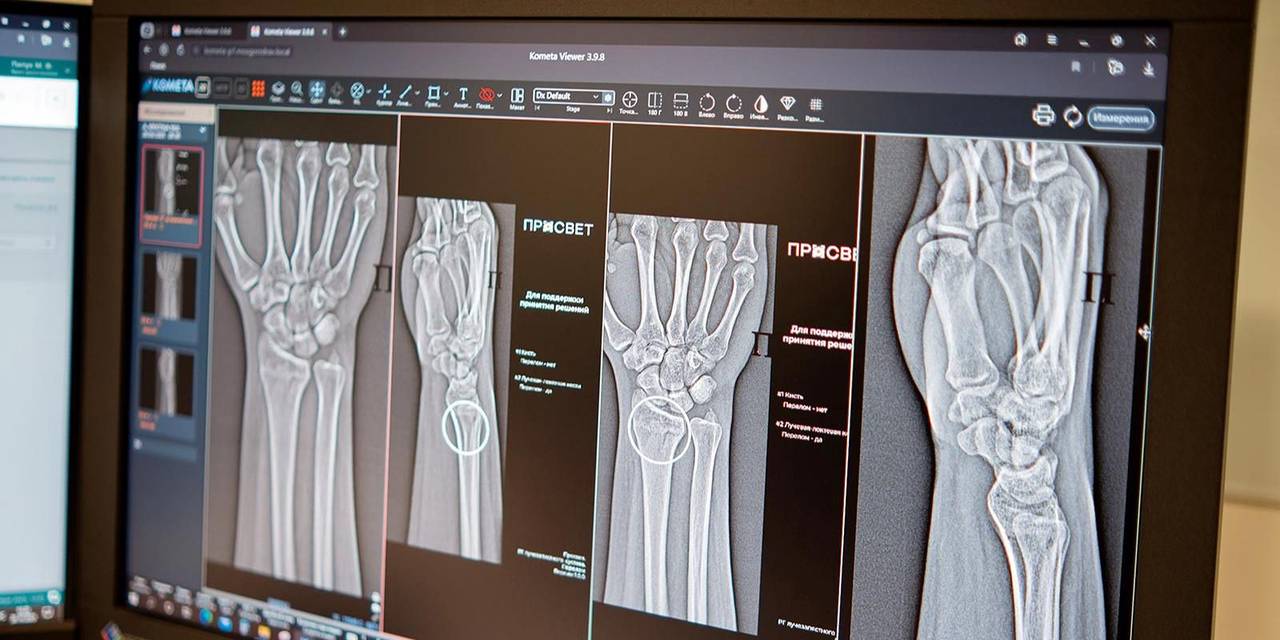

Алгоритмы автоматически идентифицируют поврежденные участки и проводят необходимые измерения, даже при наличии нескольких переломов одновременно. Сегодня московские рентгенологи располагают более чем 60 ИИ-сервисами. Некоторые из них позволяют отличить норму от патологии, другие, например, измеряют границы и размеры аномалий. Эти сервисы применяются в 43 клинических направлениях, добавила вице-мэр Москвы.

По словам главного внештатного специалиста по лучевой и инструментальной диагностике Москвы Юрия Васильева, повреждения предплечья, кисти и голени встречаются довольно часто. Процедура выявления перелома включает осмотр врача-травматолога с последующим рентгенологическим исследованием. Специалисты применяют ИИ-алгоритм как ресурс, способный повысить точность и скорость анализа лучевого изображения, что играет решающую роль в установлении диагноза.